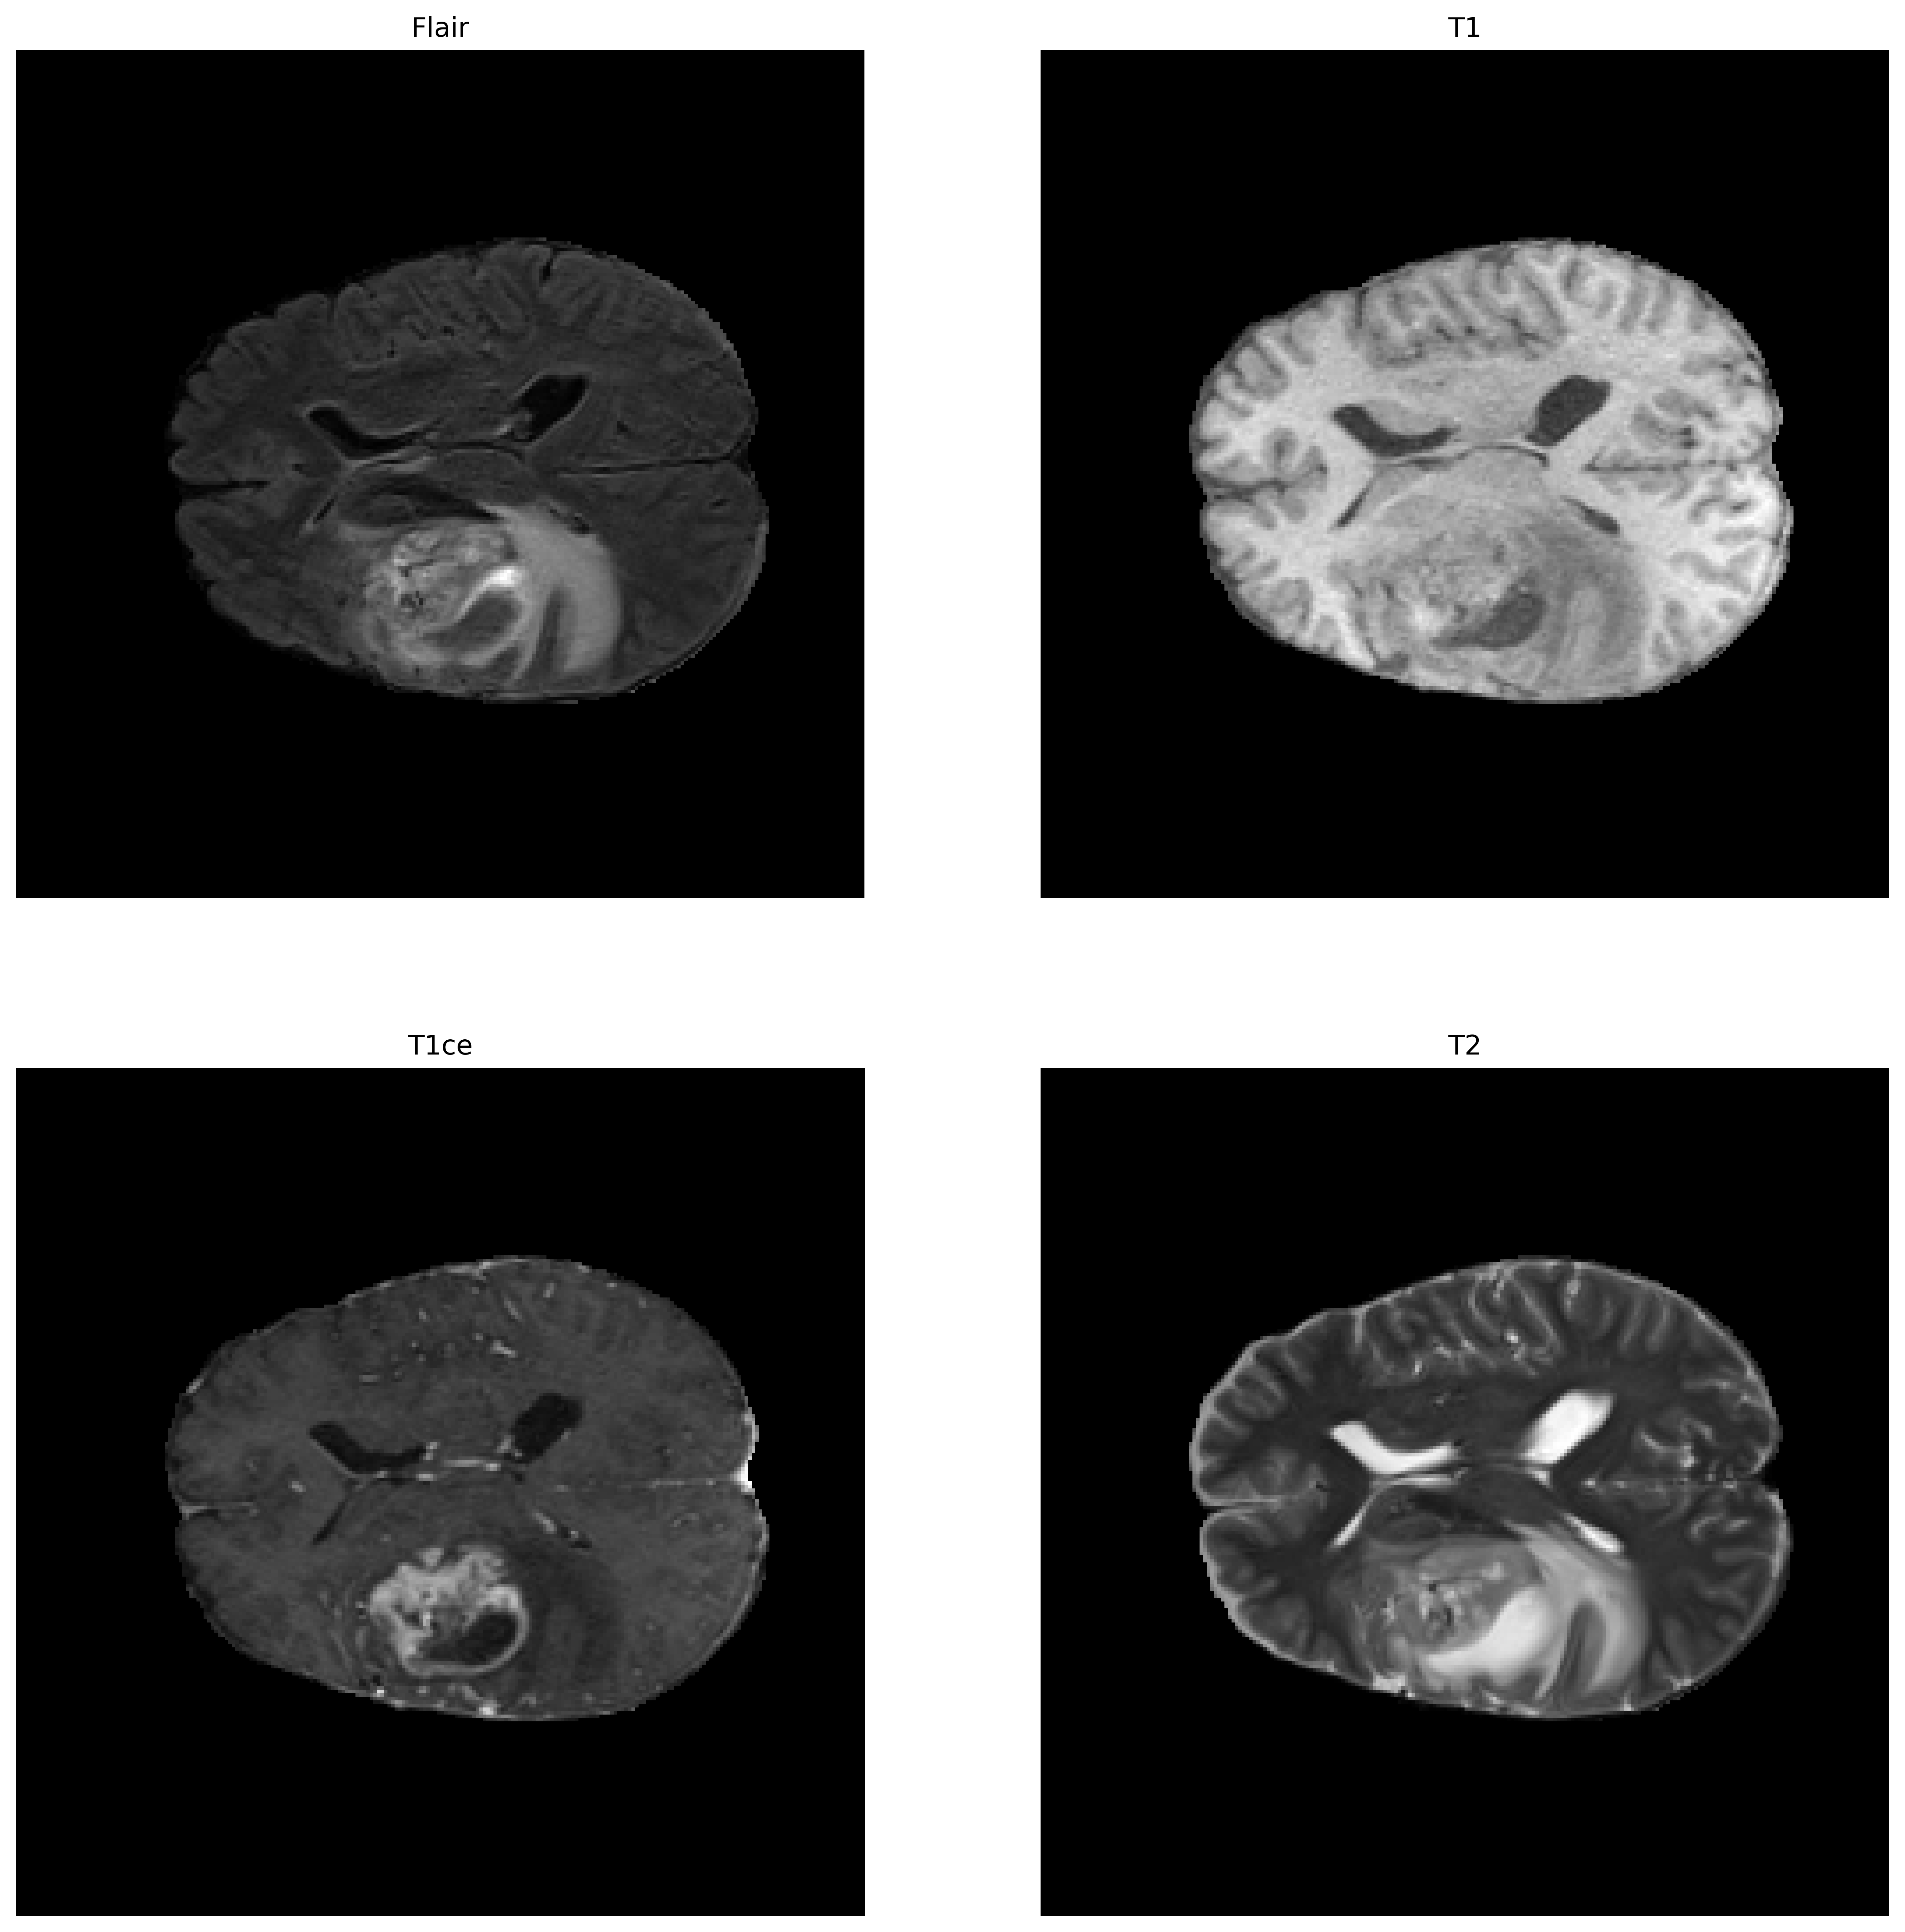

BraTS每个病例包含四个模态的磁共振成像(Magnetic Resonance Imaging,MRI),每个模态的维度为240×240×155(L×W×H)

四种模态:

-

T1

T1成像,利于观察解剖结构,病灶显示不够清晰

-

T1ce

在受试者做磁共振之前向血液内注射造影剂,使成像中血流活跃的区域更加明显,是增强肿瘤的重要判据

-

T2

T2成像,病灶显示较为清晰,判断整颗肿瘤

-

FLAIR

T2压水像(抑制脑脊液的高信号),含水量大则更亮眼,可以判断瘤周水肿区域

图片来自BraTS2021_00068号样本